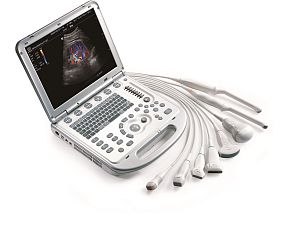

- Виды поддерживаемых датчиков: Конвексный, Микроконвексный, Линейный (до 15 МГц), Полостной конвексный, Секторный фазированный взрослый, Полостной линейный, Линейный высокочастотный.

- Типы поддерживаемых датчиков: Высокоплотный, Монокристаллический.

Переносной ультразвуковой сканер Chison Sonotouch 80 Pro применим для различных сфер - акушерства, гинекологии, урологии, ангиологии, маммологии, кардиологии, ортопедии, педиатрии, неонатологии, ветеринарии, биопсии и т.д. Аппарат выполнен в форме ноутбука с весом до 5.5 кг. Эргономичная панель управления позволяет добраться практически до любой функции за одно нажатие и имеет функцию автоподстройки подсветки в зависимости от окружающего освещения. Sonotouch 80 Pro оснащен бесштырьковым портом для подключения легковесных ультразвуковых датчиков одним движением.

Полный набор кардиологических приложений: поддержка секторного фазированного датчика, постоянно-волнового и тканевого допплера, цветного М-режима, кардиологических измерений, модуля ЭКГ.